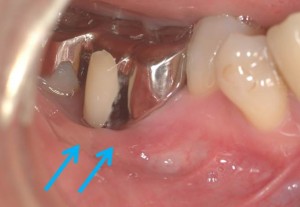

青の矢印は動く歯茎が歯の周りまで伸びてきているために、患者さんのブラッシングを邪魔します。